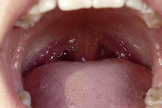

흔히 목젖 근처에 하얀색 알갱이처럼 생겨서

기침할 때 톡 튀어나오는 이 결석은

입냄새의 주범이자 만성 인후 불편감의 원인이 될 수 있습니다.

| 위치 | 입천장 뒤, 목젖 양옆에 위치한 편도(tonsil) 속 |

| 모양 | 작고 단단한 쌀알 크기의 하얀색 혹은 노란색 알갱이 |

- 목젖 양옆을 보면 하얀 점처럼 보이는 게 있다